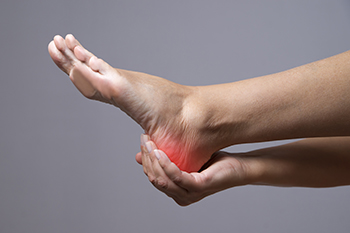

Heel pain can happen for a variety of reasons. While it can be caused by a systemic illness, such as gout or rheumatoid arthritis, it often develops from overuse. Common causes of heel pain include plantar fasciitis, heel spurs, and Achilles tendonitis. Plantar fasciitis is an inflammation of the plantar fascia, the band of tissue that runs from the heel to the toes on the sole of the foot. This can happen when the plantar fascia is overloaded or overstretched and small tears may develop. A heel spur is an abnormal bony growth at the junction of the plantar fascia and heel bone. A spur can come from strain on the plantar fascia and muscles of the foot. Achilles tendonitis is an inflammation of the Achilles tendon. It is triggered by overuse, particularly excessive jumping in sports. With all these conditions, ill fitting or worn out shoes can aggravate the problem. If you have heel pain that does not respond to rest, shoes that fit well, and are appropriate for your activity, please see a podiatrist who can properly diagnose the problem and provide treatment.

Many people suffer from bouts of heel pain. For more information, contact Barry P. Weinstein, DPM of Bellaire Podiatry. Our doctor can provide the care you need to keep you pain-free and on your feet.

Causes of Heel Pain

Heel pain is often associated with plantar fasciitis. The plantar fascia is a band of tissues that extends along the bottom of the foot. A rip or tear in this ligament can cause inflammation of the tissue.

Achilles tendonitis is another cause of heel pain. Inflammation of the Achilles tendon will cause pain from fractures and muscle tearing. Lack of flexibility is also another symptom.

Heel spurs are another cause of pain. When the tissues of the plantar fascia undergo a great deal of stress, it can lead to ligament separation from the heel bone, causing heel spurs.

Heel pain should be treated as soon as possible for immediate results. Keeping your feet in a stress-free environment will help. If you suffer from Achilles tendonitis or plantar fasciitis, applying ice will reduce the swelling. Stretching before an exercise like running will help the muscles. Using all these tips will help make heel pain a condition of the past.